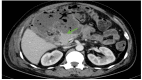

Improved insights into the pathophysiology of acute pancreatitis have paved the way for identification of distinct entities in the spectrum of the disease. The presence of necrotising inflammation limited to peripancreatic tissue with a normal appearance of pancreas is one such entity. This entity, described as extrapancreatic necrotising pancreatitis (EPN), is considered a less aggressive form of acute necrotising pancreatitis. This entity needs to be recognized precisely and managed accordingly among patients with acute pancreatitis. However, EPN has not been highlighted in the revised classification of acute pancreatitis. Here we report two patients with EPN with varied presentations and diverse management and outcome.